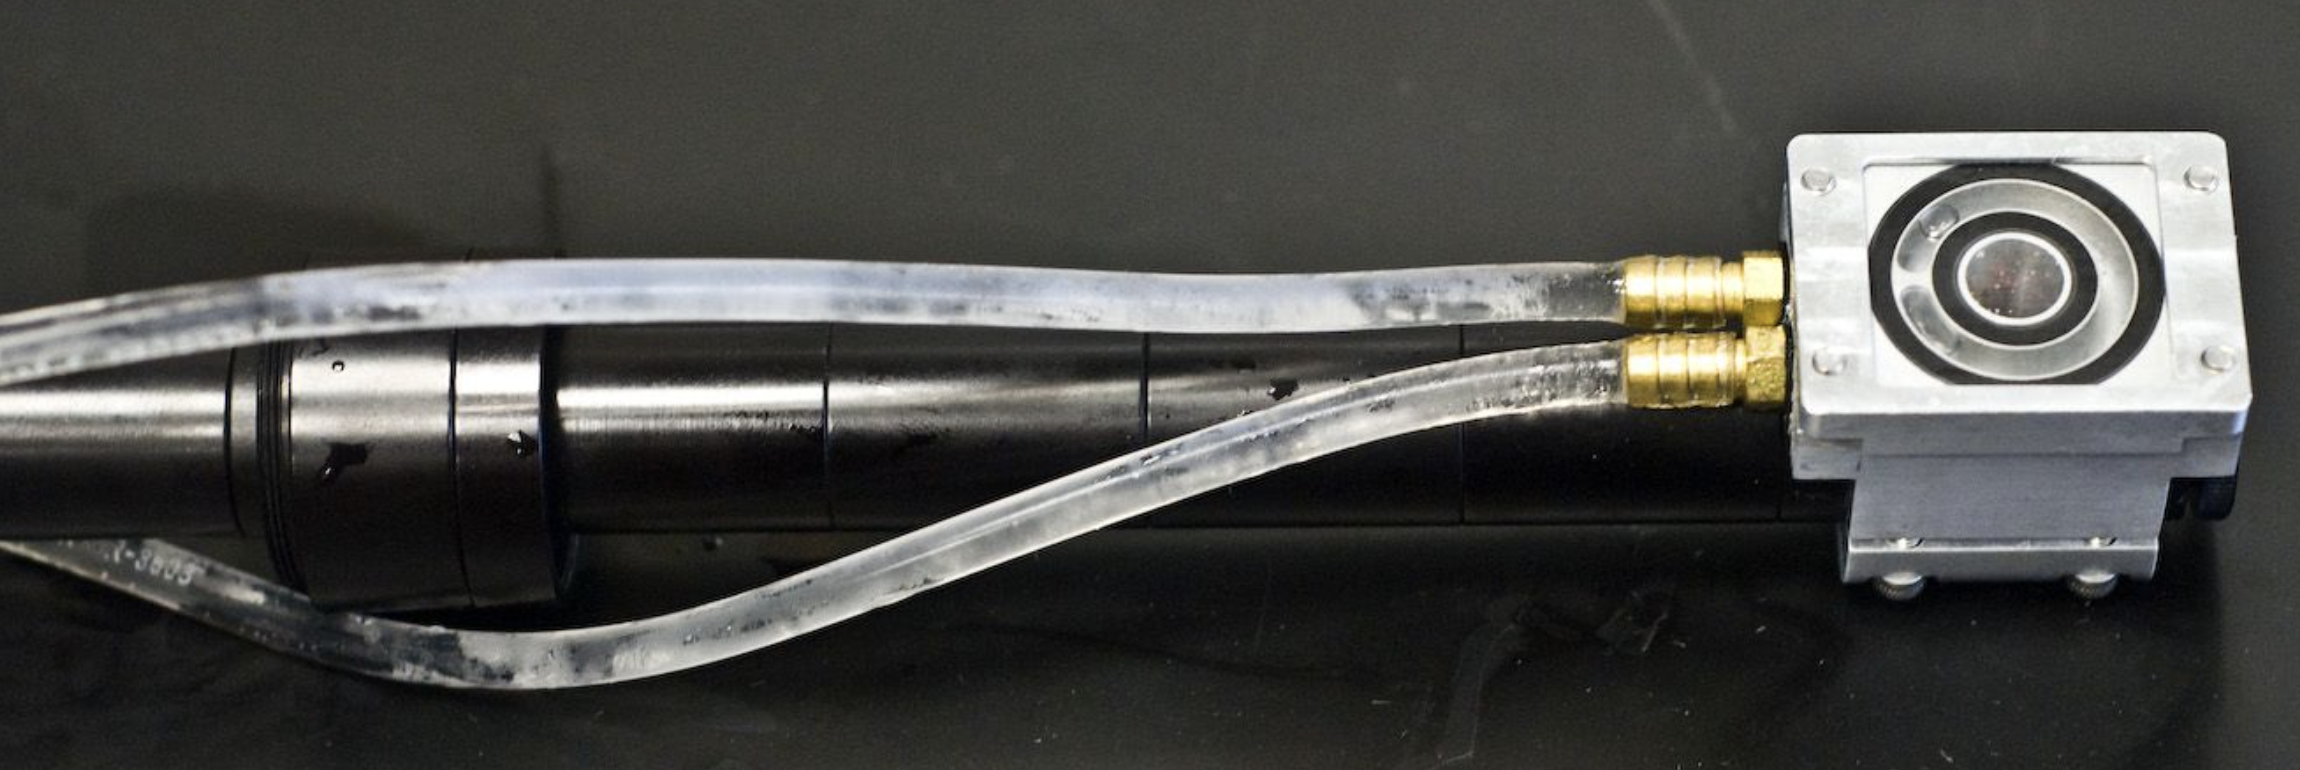

-biomedical optics

-laser/tissue interactions

-pulsed Er:YAG laser scalpel

-ophthalmology/cataracts

-kidney/urinary stones

-other urology